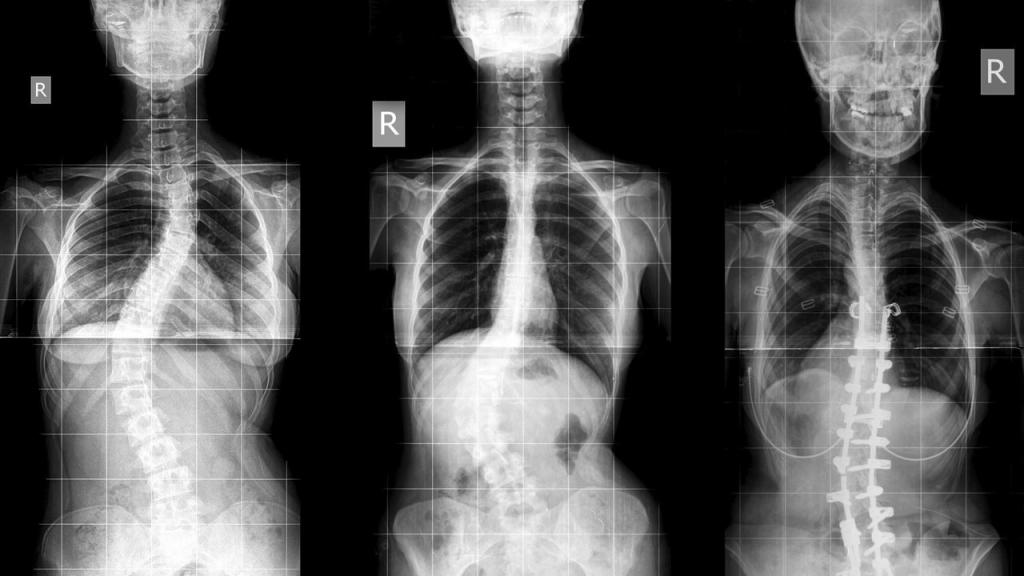

Сколиоз

Это деформация позвоночника. Она бывает врожденной и не врожденной, приобретенной (в итоге нарушения осанки или травм). При сколиозе нежелательно:

- длительно стоять и сидеть в неудобной позе;

- быстро бегать (именно по этой причине запрещены виды спорта, которые предусматривают бег);

- переносить тяжести в одной руке;

- совершать круговые движения;

- носить тесную одежду.

Каким спортом нельзя заниматься при сколиозе? Нельзя заниматься быстрым бегом (категорически любой бег запрещен при сколиозе 3-4 степени), гимнастикой, танцами, подвижными спортивными играми (футболом, баскетболом и т.д.), а также прочими спортивными категориями, предусматривающими названные выше нежелательные действия.

Если говорить именно о спортивных упражнениях, то категорически запрещены:

- упражнения, выполняющиеся на одной ноге;

- поза лотоса;

- кувырки;

- упражнения, предусматривающие вертикальную осевую нагрузку на позвоночник и круговые движения с поворотами.

Все запрещенные упражнения и виды спорта могут привести к значительным осложнениям болезни: переходом степени сколиоза в другую, более сложную; боли; еще большему ухудшению осанки. Одним словом, рекомендациям необходимо следовать, чтобы не усложнять себе жизнь.